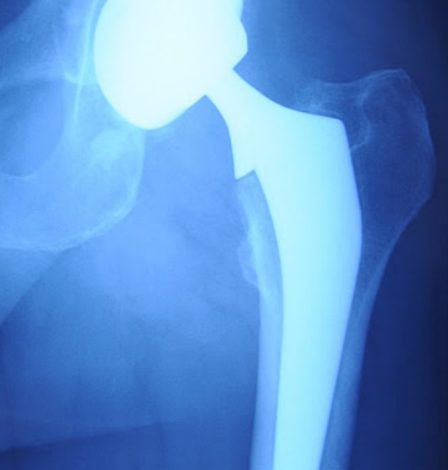

La protesi nel tempo può usurarsi o mobilizzarsi con perdita della tenuta dell’ impianto nell’osso ; in tale situazione è necessario eseguire un reimpianto che può essere totale o parziale. Si tratta di una chirurgia impegnativa i cui risultati dipendono dalla esperienza del chirurgo ma soprattutto dalla qualità dell’osso. L’intervento ha una durata maggiore rispetto al primo impianto ; il post- operatorio è in genere più impegnativo e sicuramente più lungo. Ogni singolo caso deve essere preceduto da un attento studio clinico-radiografico per pianificare un protocollo chirurgico che sarà specifico per il paziente da trattare.